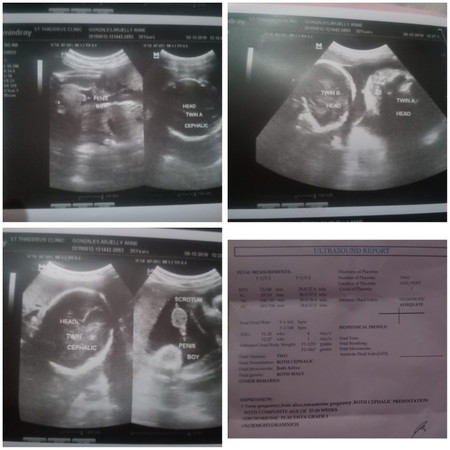

Twin

Mga sis pa advice naman sa mga naka panganak ng kambal dyan na normal. ano pong ginawa nyo? pa advice naman po mga sis kinakabahan tlga ko. wla kasi kaming lahing kambal kaso ung side nila lip meron. pang 2nd baby kona to mga sis. sa panganay ko normal delivery naman. gusto ko din sanang mainormal tong kambal.

Full time mom and 6 months pregnant for my 2nd baby